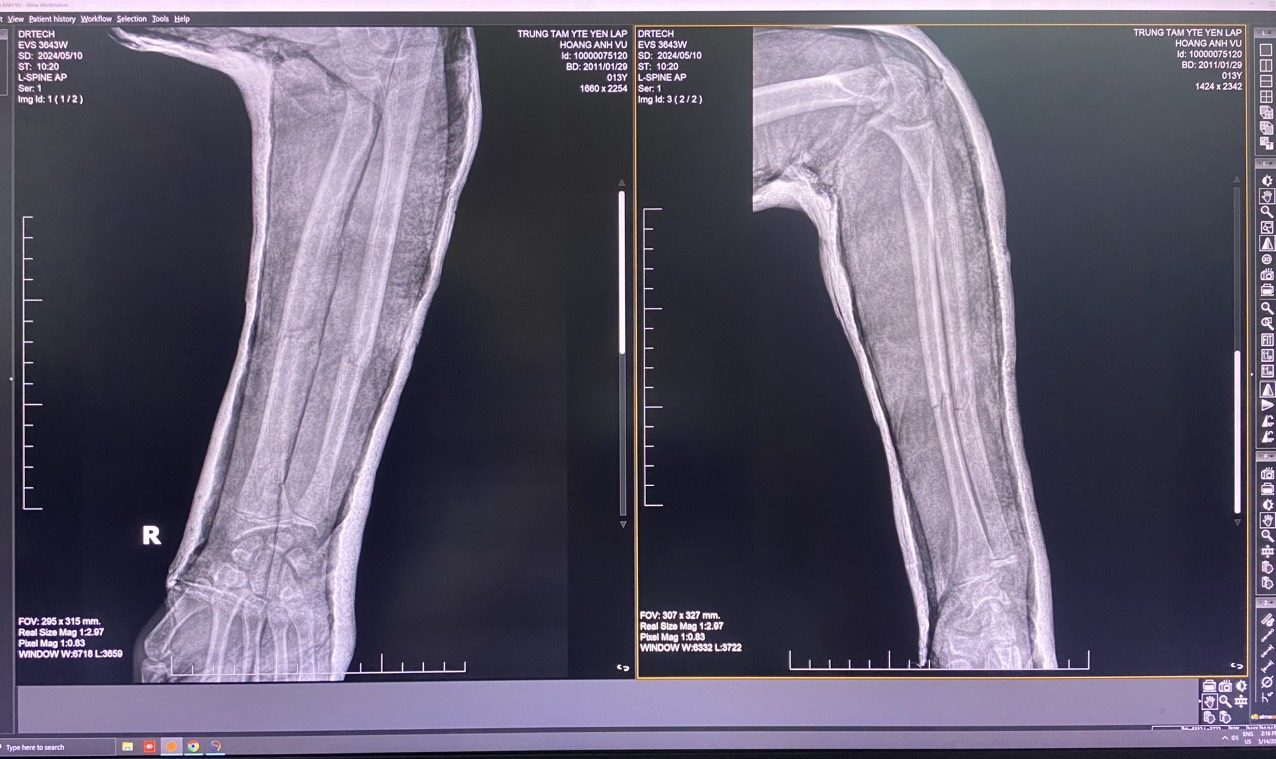

Qua thăm khám lâm sàng, các bác sỹ thấy cẳng tay phải của người bệnh sưng nề, có điểm đau chói, lệch trục, vận động hạn chế. Qua kết quả chụp Xquang cho thấy hình ảnh gãy dạng gập góc 1/3 giữa xương trụ và xương quay cẳng tay phải.

Kết quả chụp Xquang cho thấy hình ảnh gãy dạng gập góc 1/3 giữa xương trụ và xương quay cẳng tay phải